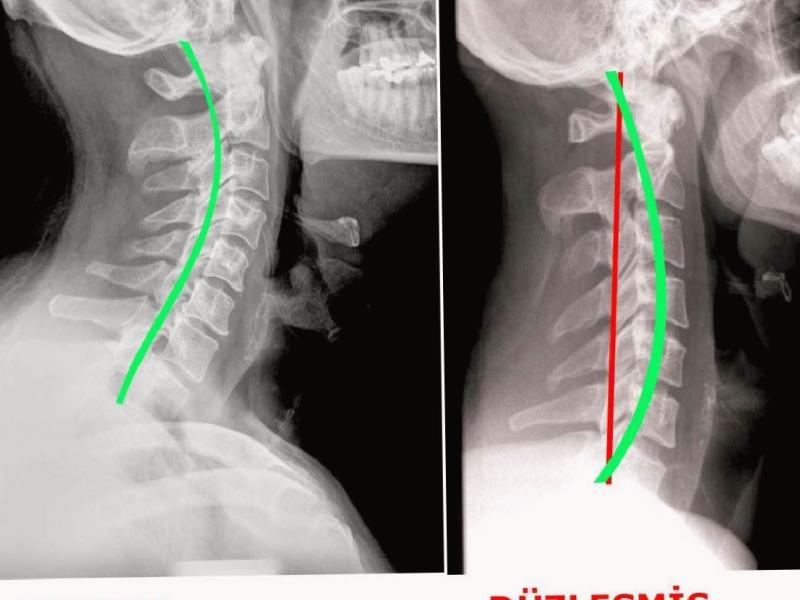

Neck flattening; This is because the spine, which looks like an inverted C (left figure in the picture), takes the I shape (right figure in the picture) for various reasons. It is generally a condition that occurs after spasm and tension in the neck muscles. It develops after not using suitable pillows, using technological devices such as mobile phones for a long time and looking at the computer screen for long periods of time.